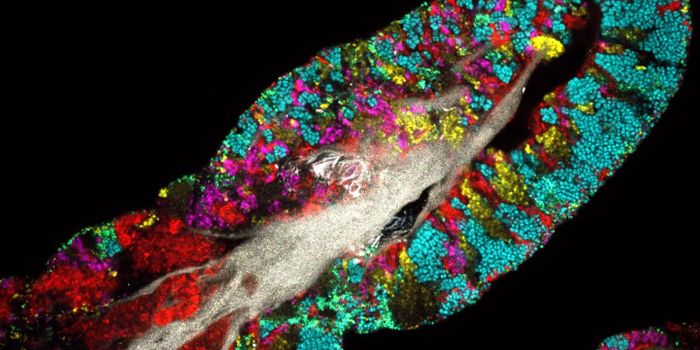

MAR 17, 2015CancerVanderbilt University researchers have achieved the first "image fusion" of mass spectrometry and microscopy - a technic ...